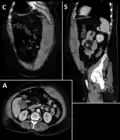

Rectus sheath hematoma seen on axial CT – with active bleeding under Marcoumar - Rectus sheath hematoma as seen on ultrasound[5]